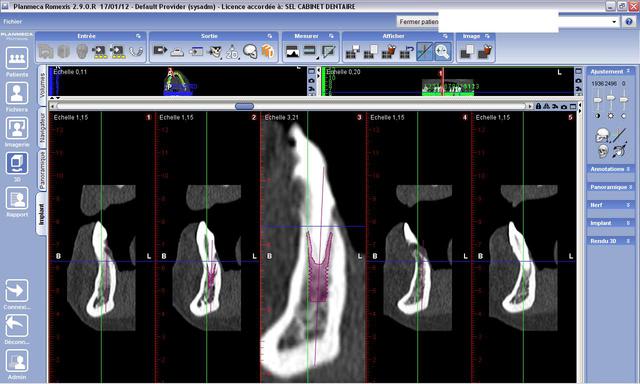

Voici le cas en image

Mon doute portait donc sur la face vestibulaire de l'implant en place de 43.

Implant4.5*11 Astra